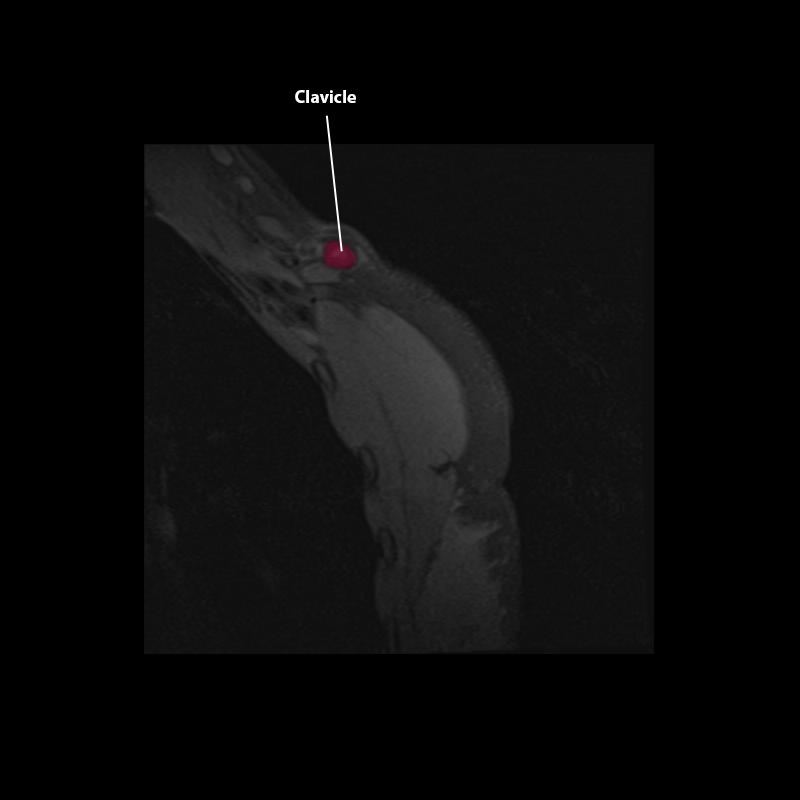

Shoulder MRI Anatomy